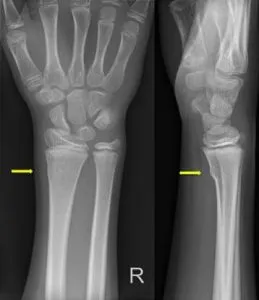

- Röntgenfoto: dit is het belangrijkste onderzoek. Op de foto is doorgaans duidelijk te zien of er een breuk is en wat voor type. Bij kinderbreuken kijkt men goed naar afwijkingen in de contour van het bot: een buiging of kleine breuklijn kan al duiden op een greenstick of torusfractuur. Ook wordt gelet op de groeischijven om te zien of die vrij zijn van letsel.

- Greenstick-fractuur (groenhoutbreuk): het bot is aan één zijde gebroken en aan de andere zijde alleen gebogen, net als een jong groen takje van een boom dat je breekt. Het bot blijft gedeeltelijk intact.

- Torusfractuur (twijgbreuk): hierbij is het bot niet echt gebroken, maar ingedeukt of geplooid, alsof het bot een deukje heeft opgelopen. Dit komt vaak voor aan het uiteinde van de onderarmbeentjes bij een val.